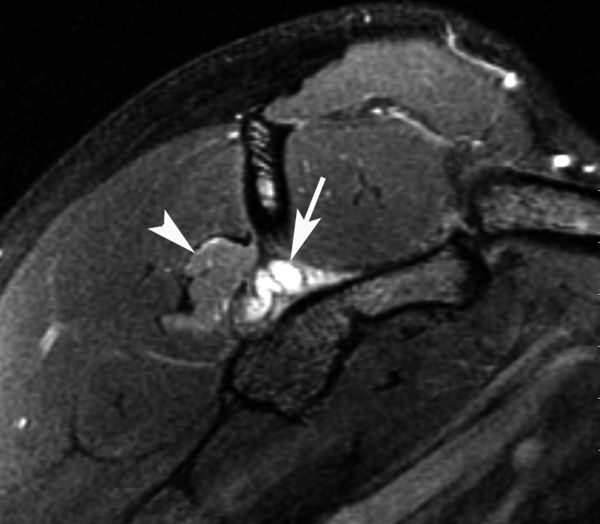

In some cases, Type II SLAP lesions may be associated with the formation of a paralabral cyst. Paralabral cysts associated with Type II SLAP lesions are usually formed in the posterior superior quadrant of the labrum and therefore forms the classical spinoglenoid cyst.

When large, spinoglenoid cysts may encroach upon the suprascapular nerve and result in neuropathy (Figure 3). Unlike suprascapular neuropathy due to compression at the suprascapular notch, suprascapular neuropathy from a spinoglenoid cyst usually results in isolated infraspinatus atrophy and weakness and spares the supraspinatus.

Selective compression of infraspinatus branch of suprascapular nerve.

Figure 3. MRI sagittal view of a spinoglenoid cyst lesion with T2 sequences. Note the infraspinatus edema reflecting suprascapular nerve compression. Reproduced from XX with permission.

However, a selective compression of the supraspinatus branch is possible (Figure 4).

Selective compression of supraspinatus branch of suprascapular nerve.

Figure 4. Left: MRA coronal view with T2 sequences revealing a large spinoglenoid cyst. Right: MRI sagittal view of the same patient with T1 sequences of a fatty infiltrated supraspinatus. Reproduced from XX with permission.